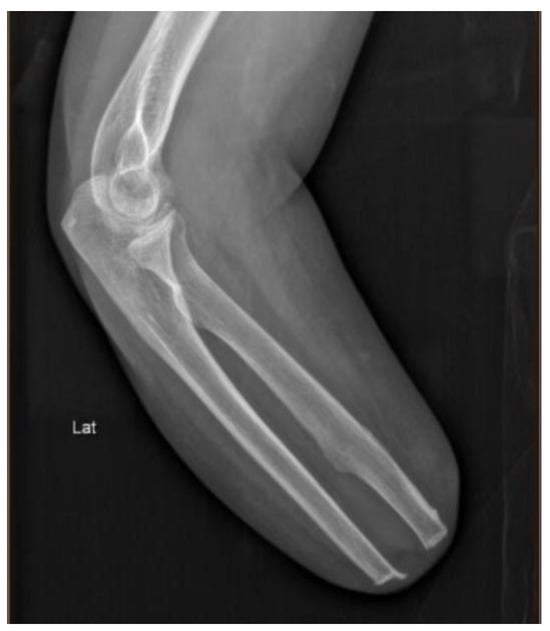

The subject, Min Xu, female, born in November 1975, underwent a unilateral (right), transradial amputation. The amputation occurred in 1992, when the subject was at the age of 17, as a result of a factory punching machine accident (X-ray images provided in Figure 1). Before the incident, she was right-hand dominant. In 2000, the subject briefly used a cosmetic prosthesis for her wedding. However, she quickly abandoned it because of discomfort, specifically finding the socket unbearable hot and stifling. She did not use any prosthetic devices again until January 2023, when she began training for the CYBATHLON 2023 Challenge. This marked her first experience with functional prostheses. As a pilot, she successfully participated in the CYBATHLON Challenge events in March 2023 and February 2024, as well as CYBATHLON 2024. Prior to her participation in prototype testing, the training was approved by the regional Ethics Committee, and she signed an informed consent (Supplementary File S1). The ethical approval and device risk analysis was reviewed by the organizing committee of the CYBATHLON before the subject was granted permission to participate in competition.

Figure 1. X-ray of forearm amputation (right hand), lateral view (lablled “Lat”).